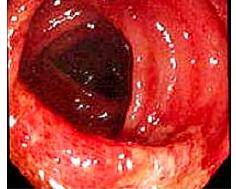

老年人缺血性結腸炎內鏡檢查主要根據其有可能的致病因素或病因相應的臨床表現 一系列結腸X線及內鏡檢查。臨床須與菌痢、潰瘍性結腸炎、假膜性小腸炎相鑑別。

2.纖維結腸檢查 對本病的早期診斷有重要價值,但應注意壞疽型不宜做結腸鏡檢查。其鏡下表現為:

(1)急性期:起病72h以內 ,黏膜充血、水腫,多見散在出血點淺表糜爛,約半數可有淺表潰瘍,病變呈節段性分布界限清楚;活檢可見炎細胞浸潤鶒,小血管內纖維素樣血栓形成腺管破壞及灶性出血

(2)亞急性期:起病72h至7天,可見典型縱行潰瘍形成,並可見明顯的炎性滲出物;活檢可見組織壞死及肉芽修復。

(3)慢性期:起病後兩周至兩個月,鏡下僅見輕度炎症改變無特徵性。活檢整體退行性變纖維組織及肉芽組織增生並可見較特異的含鐵血黃素沉著